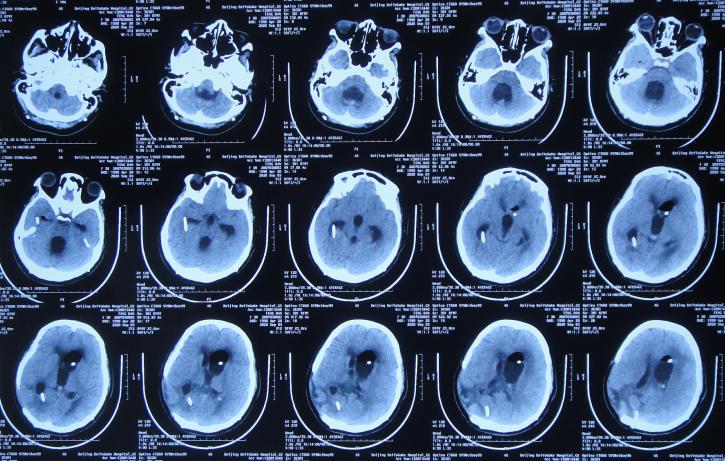

开颅术后次日即2020年4月3日,意识恢复,可简单言语,但左侧肢体偏瘫,仅可在床面平移,伴发热体温最高39.0℃;复查头颅CT示开颅术后去骨瓣状态,出血有减少,引流术后状态( 图-2 )。

图-2: 2020年4月3日头颅CT

开颅术后第3天即2020年4月5日,因出血明显减少,拔除了脑室外引流管( 图-3 )。

图-3: 2020年4月5日头颅CT